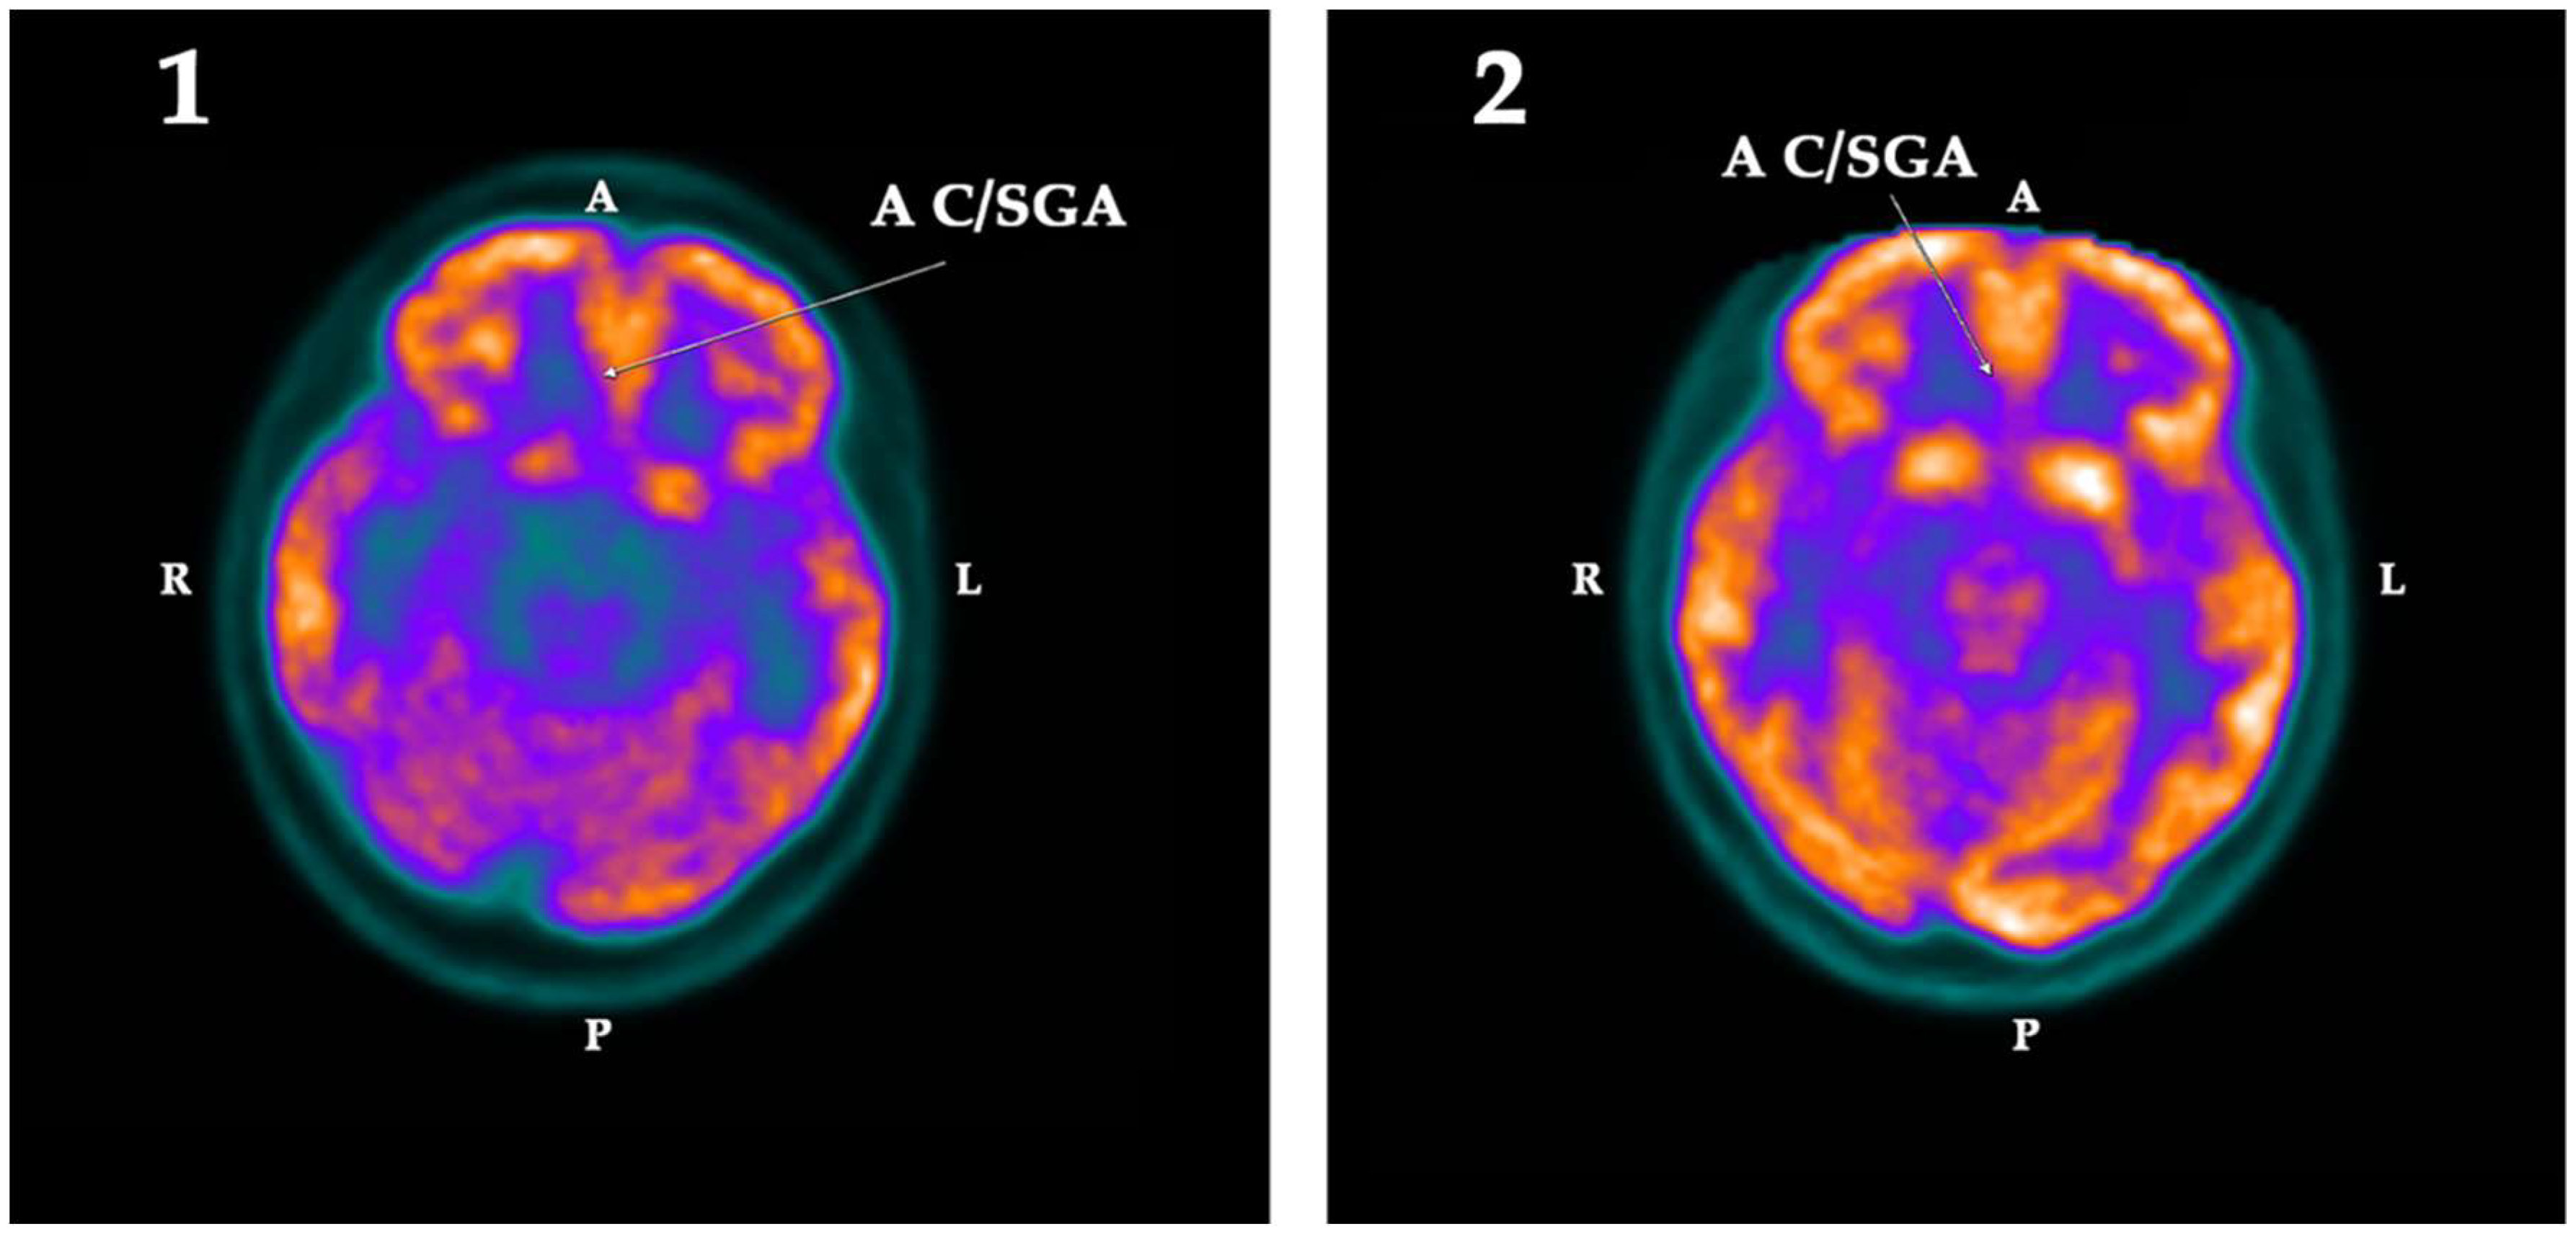

2.2. PET-SCAN Studies

| ROI | First PET-SCAN | p < | Second PET-SCAN | ||||||

|---|---|---|---|---|---|---|---|---|---|

| L | R | Asym | Hypom | L | R | Asym | Hypom | ||

| AC/SGA | −2.43 | −11.16 | 8.73 | Right | 0.025 | 3.08 | 0.91 | −2.17 | |